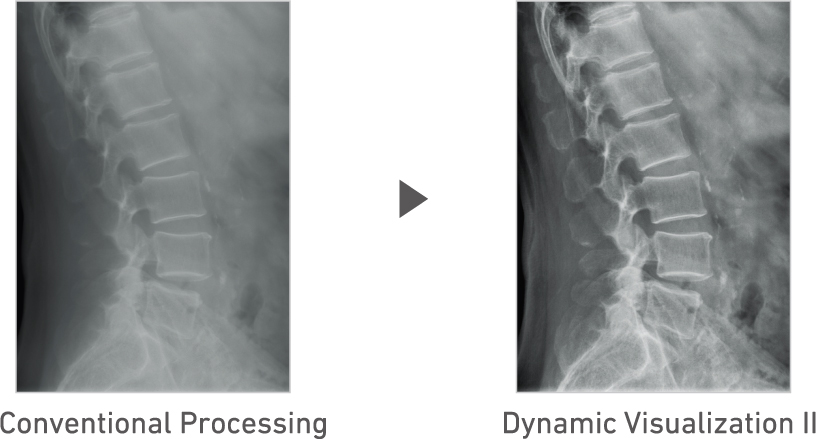

Advanced recognition algorithms automatically adjust contrast and density for individual body parts based on calculation of estimated 3D image data.*5